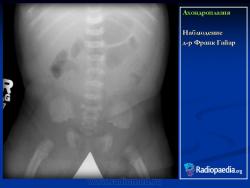

Наблюдение д-ра Франк Гайар

Ахондроплазия

Случай 2: полная длина